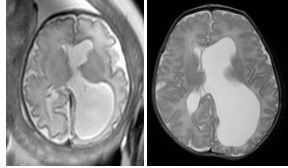

hydrocéphalie associée à une lissencéphalie de type double cortex - des lésions extra-cérébrales parfois dans le cadre d’un syndrome polymalformatif (spina bifida, infection materno-foetale)